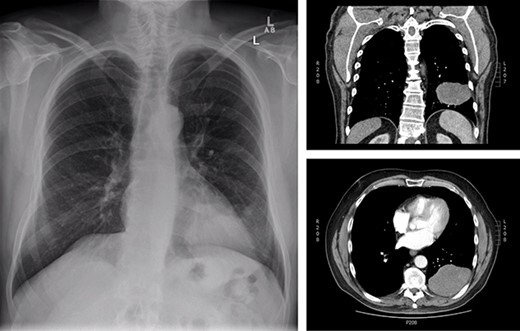

The patient is a 70-year-old man with a 75-pack-year smoking history and occupational asbestos exposure, who presented with back pain and constitutional symptoms in 2019. Physical exam was unremarkable except for hypertrophic pulmonary osteoarthropathy with digital clubbing. Computed tomography chest demonstrated a 18.3 × 17.0 × 13.8 cm left pleural-based tumour, with heterogeneous density and internal calcifications, resulting in compression of the left lower bronchi (Fig. 1). The patient’s medical records revealed that he was originally diagnosed with a left-side pleural SFT in 2013 (Fig. 2); imaging and biopsy at that time revealed a 9.3 cm spindle cell tumour consistent with SFT. The patient was lost to follow-up.

Representation of solitary fibrous tumour in 2019 showing 18.3 × 17.0 × 13.8 cm left-sided pleural-based tumour.

Initial presentation of solitary fibrous tumour in 2013 showing 9.3 × 6.1 cm left-sided pleural-based tumour.